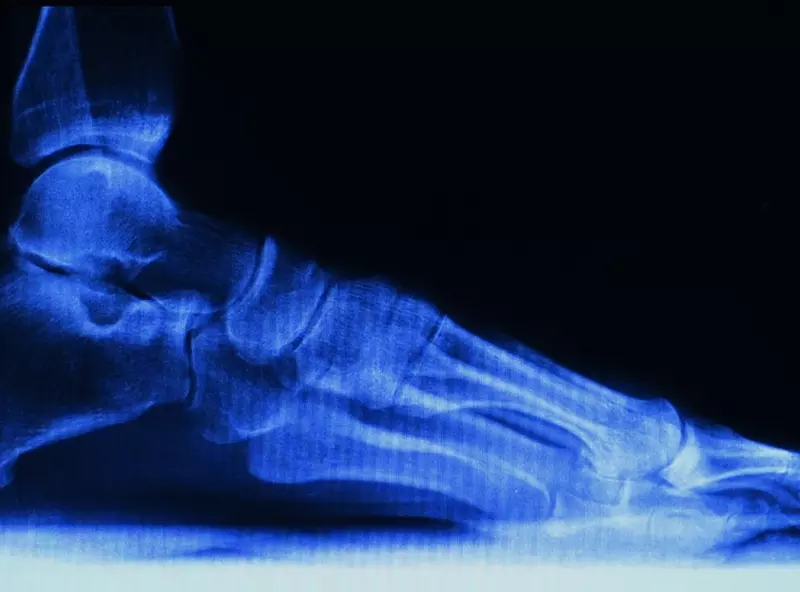

Anatomia

Cały kompleks odpowiadający za stabilność stawu skokowego jest niezwykle złożonym mechanizmem, którego każdy element pełni ważną funkcję. Składa się z 26 kości utrzymywanych przez równie liczne i silne więzadła.

Staw skokowy górny, inaczej nazywany skokowo-goleniowym, jest stawem zawiasowym, mającym jeden stopień swobody ruchu. Stanowi połączenie kości piszczelowej oraz strzałkowej z bloczkiem kości skokowej. Na górnej części kości skokowej znajduje się powierzchnia stawowa górna (dzielona na kostkową przyśrodkową oraz kostkową boczną), która przylega do powierzchni stawowej kości piszczelowej oraz strzałkowej. Więzadła zaopatrujące staw skokowy górny po stronie bocznej to: